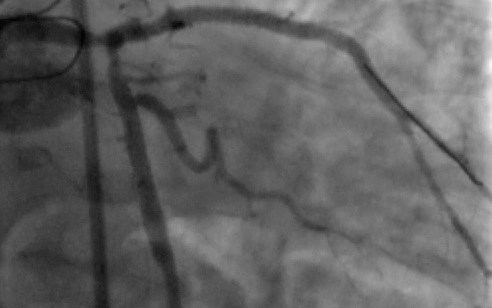

La aterectomía rotacional para tratar lesiones coronarias

Esta técnica permite tratar pacientes complejos con buenos resultados a largo plazo

Se trata de un procedimiento que elimina las obstrucciones existentes en las arterias coronarias. Los doctores Juan Vicente Herrero Vilar y Eva Rumiz González, especialistas de la Unidad de Hemodinamia y Cardiología Intervencionista del Hos...